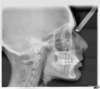

Téléradio